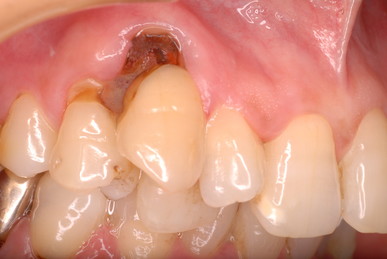

二ヶ月後ですが、歯周病が酷くなったので一時的に矯正治療を中止しました。歯周ポケットの深さを測っています。

挿入したゴムのポイントです。

歯並びは綺麗になり掃除はしやすくなったはずですが、矯正治療中は

磨きにくいので歯周病や虫歯が酷くなりやすいのです。